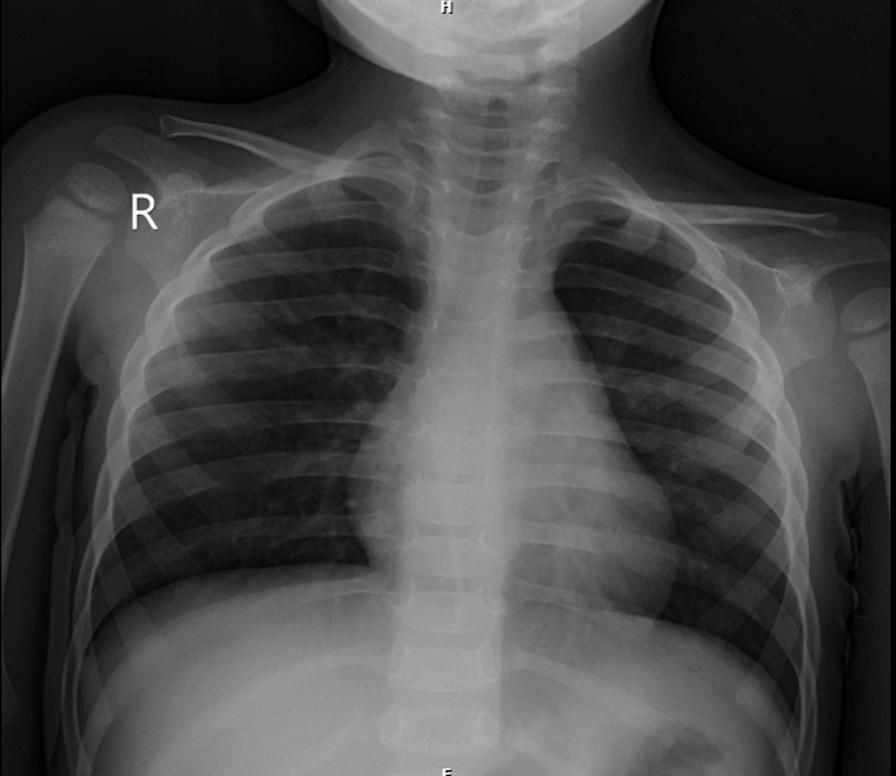

Here, we report a 2.5-year-old Iranian boy who presented with bilateral corneal xerosis and corneal opacity secondary to vitamin A deficiency related to cystic fibrosis malabsorption.

这里,我们报告了一名 2.5 岁的伊朗男孩,因囊性纤维化吸收不良导致维生素 A 缺乏,出现双眼角结膜干燥症和角膜混浊。